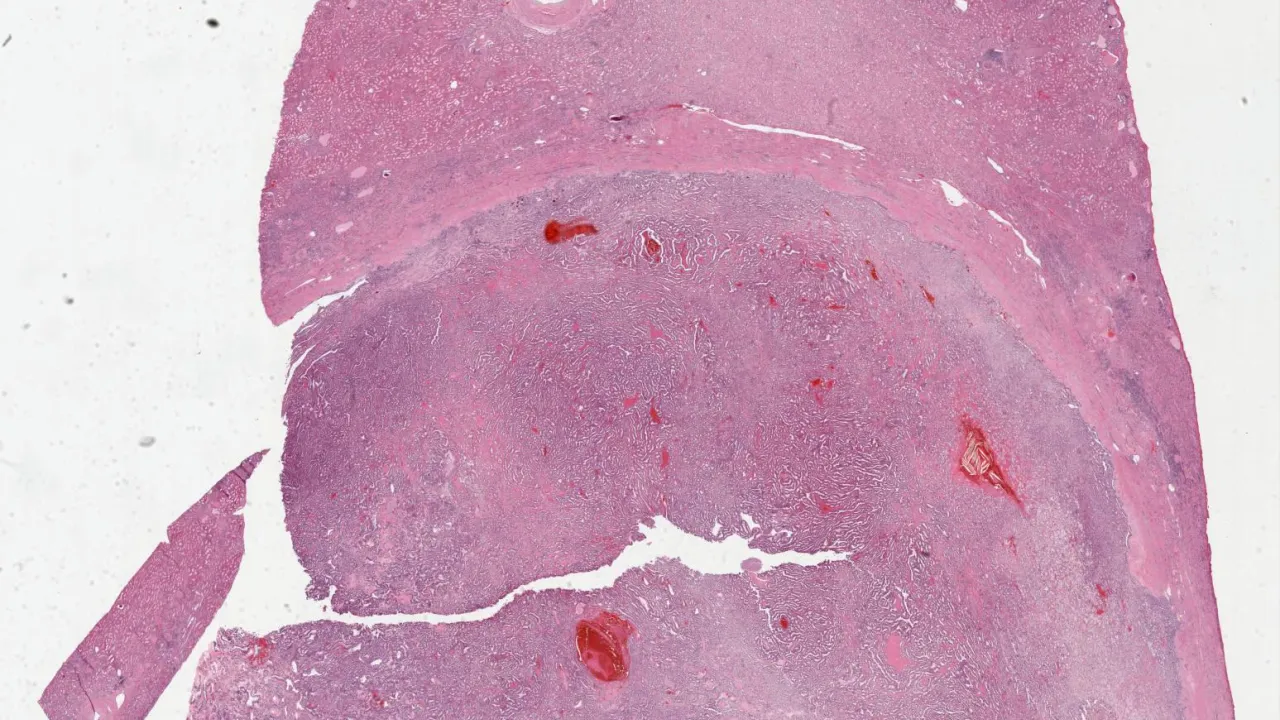

Kidney, Multilocular cystic renal neoplasm of low malignant potential